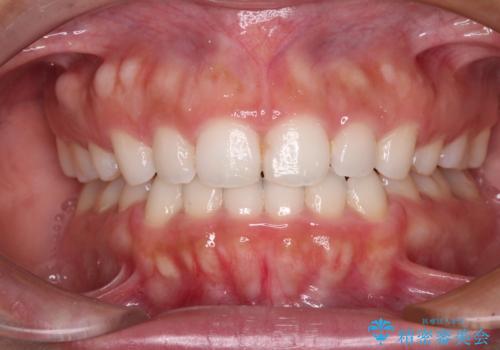

上顎歯列全体がスムーズに後方移動でき、1年で治療を終えることができました。